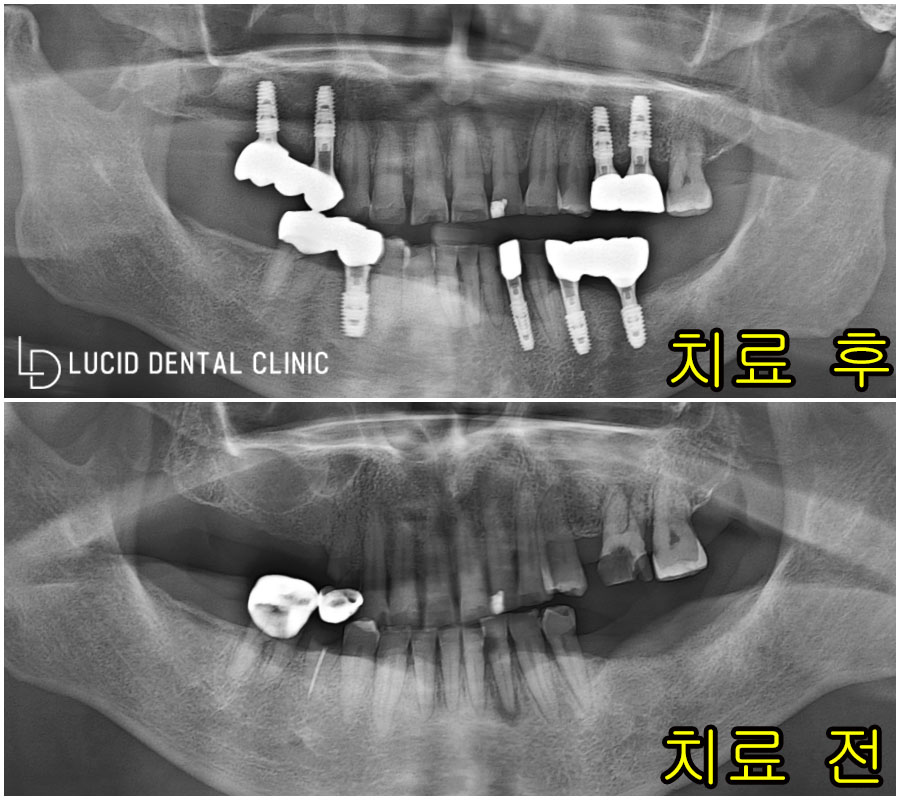

위와 같은 검진 결과를 바탕으로

치료 계획을 수립해 봤는데요

논현동 치과 에서 수립한 치료 계획은

바로, 다수의 임플란트 식립이었습니다.

치료 도중 치조골 소실이 일어난 부분에는

추가로 골이식 과정을 함께 시행하였는데요

코 양쪽 위치에 자리 잡고 있는

해부학 구조, 상악동 막을 들어 올린 뒤

필요한 양만큼 인공 뼈 재료를 채워 넣어

단단한 고정력을 유도하였습니다.

이후 임플란트 픽스처를 즉시 식립하며

온전히 회복될 때까지 기다리기로 했는데요

치료 부위가 온전히 회복된 모습을

확인한 다음, 인상 채득 및 보철 제작에 들어갔고

제작된 보철을 장착한 다음,

위와 같은 모습으로 치료를

종료할 수 있었습니다 :)

상악동 골 이식을 진행한 부위도

잘 유착되어 단단한 고정력을 보여주었고,

소실된 치아 기능은 물론,

주변 치아와의 유사한 색조로

저도, 환자도 만족스러운

치료 결과를 가질 수 있었죠.

위와 같이 치료 전/후 사진을 통해

그 차이를 느끼실 수 있을 겁니다.